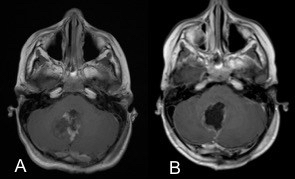

elle peut être très évocatrice, montrant une tumeur spontanément hyperdense en scanner, avec une prise de contraste hétérogène et une hypercellularité bien montrée par la séquence en diffusion.

l’aspect radiologique peut cependant être trompeur.

on recherche systématiquement des métastase par l‘IRM cranio-spinale.